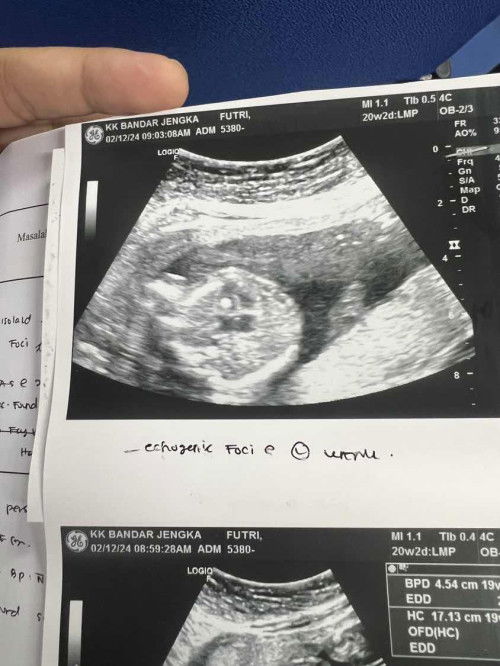

Tanda putih pada jantung baby

Scan Baby semua normal . Cuma ada tanda putih pada jantung dia . Doc kata masuk 3rd trimester tanda putih tu akan hilang . Ada ibu2 pernah mcm saya ? Boleh share tak ? Saya risau sgt2